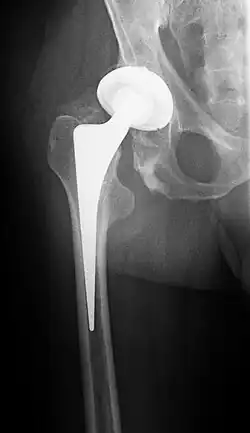

![]() Radiografía de una artroplastia de cadera | ||

Una prótesis de titanio, con una cabeza cerámica y copa acetabular de polietileno. El reemplazo total de cadera, conocido en términos médicos como artroplastia de cadera, consiste en la cirugía ortopédica que busca reemplazar de forma total la articulación de la cadera con un implante artificial llamado prótesis.